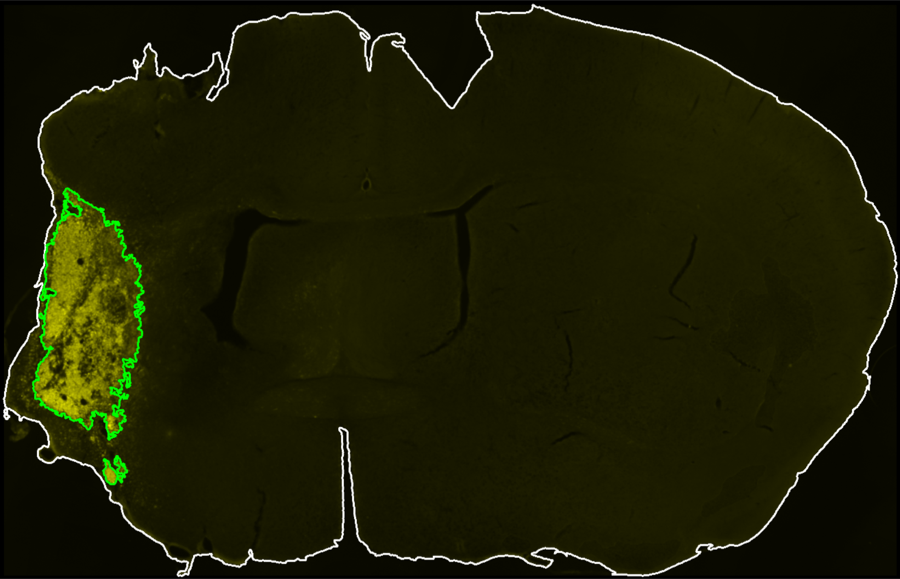

Segmentation Workflow

A GUI with interactive controls defines midline placement, brain contour thresholds, CD68 thresholds, and exclusion-channel thresholds for section-level infarct segmentation.